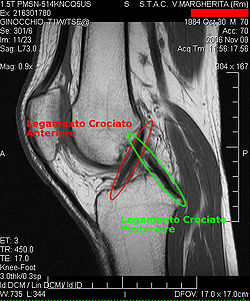

Procédés d'imagerie

Le diagnostic peut être confirmé par imagerie (IRM). Mais il faut noter que l'interprétation de l'IRM seule pour le diagnostic de rupture de LC conduit à 20 % de faux diagnostics. Cela dépend des images de coupe et de la position appropriée du genou pendant l'IRM. Le radiologue doit connaître avec précision les circonstances qui ont conduit à la blessure, et avoir aussi une bonne expérience de l'étude d'une articulation blessée, pour éviter les faux diagnostics. Pour comparer avec l'IRM, le taux d'erreur du test de Lachman, bien plus simple à accomplir, n'est que de 10 %[108],[109],[110],[111]. L'IRM est donc généralement moins sensible et moins spécifique que l'examen clinique par un orthopédiste qualifié[112]. Le résultat de l'IRM n'a que relativement rarement une influence sur la formulation finale du diagnostic[113] et ne devrait pas servir de remplacement pour une anamnèse soigneuse et la palpation[114]. Plusieurs études arrivent à la conclusion que l'IRM n'a de sens que pour des blessures complexes difficiles à expliquer, et là, pour éviter de poser un diagnostic négatif[115],[116],[117].

Les radios n'apportent aucune contribution immédiate au diagnostic de rupture de LC. Les deux LC sont invisibles à la radio, déchirés ou non. La seule utilité de la radio ne peut servir qu'au diagnostic des complications osseuses possibles.